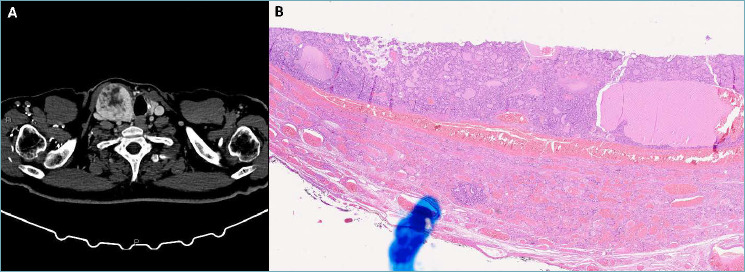

Hepatocellular carcinoma typically metastasizes within the liver and may involve extrahepatic sites such as the lungs, adrenal glands, and bones at advanced stages. However, hepatocellular carcinoma metastasis to the thyroid is very uncommon and tumor-to-tumor metastasis from a hepatocellular cancer to a thyroid neoplasm is extremely rare. In this report, we present a case of a 70-year-old man with a hepatocellular carcinoma metastasizing to oncocytic thyroid carcinoma, emphasizing the importance of clinical history and of a multidisciplinary approach, as well as the usefulness of site-specific immunohistochemical markers, in diagnosing and managing cases of Rosai's metastasis, especially when donor and recipient neoplasms share similar histologic features.

Abstract Image